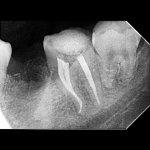

• مجهز به دستگاه apex locator morita تمام دیجیتال ساخت ژاپن جهت دقت ۱۰۰ درصدی در تشخیص عصب های ریز باقی مانده

• مجهز ب سیستم دیجیتال rvg جهت بررسی وجود عصب های فرعی و کوچک در مانیتور

• مدرک تخصصی عصب کشی های پیشرفته

• ارائه فاکتور به همراه عکس بعد از عصب کشی برای بیمه های تکمیلی ( به صورت مستقیم با بیمه تکمیلی قرار داد ندارند)

• عصب کشی تخصصی تمامی دندان ها

عصب کشی 1 کانال 3800

عصب کشی2 کانال 4600

عصب کشی 3 و 4 کآنال 5900

عصب کشی مجدد یا عصب کشی تخصصی قیمت باتوجه به گرافی مشخص میگردد(معمولا 1 تا 2 میلیون گران تر است)